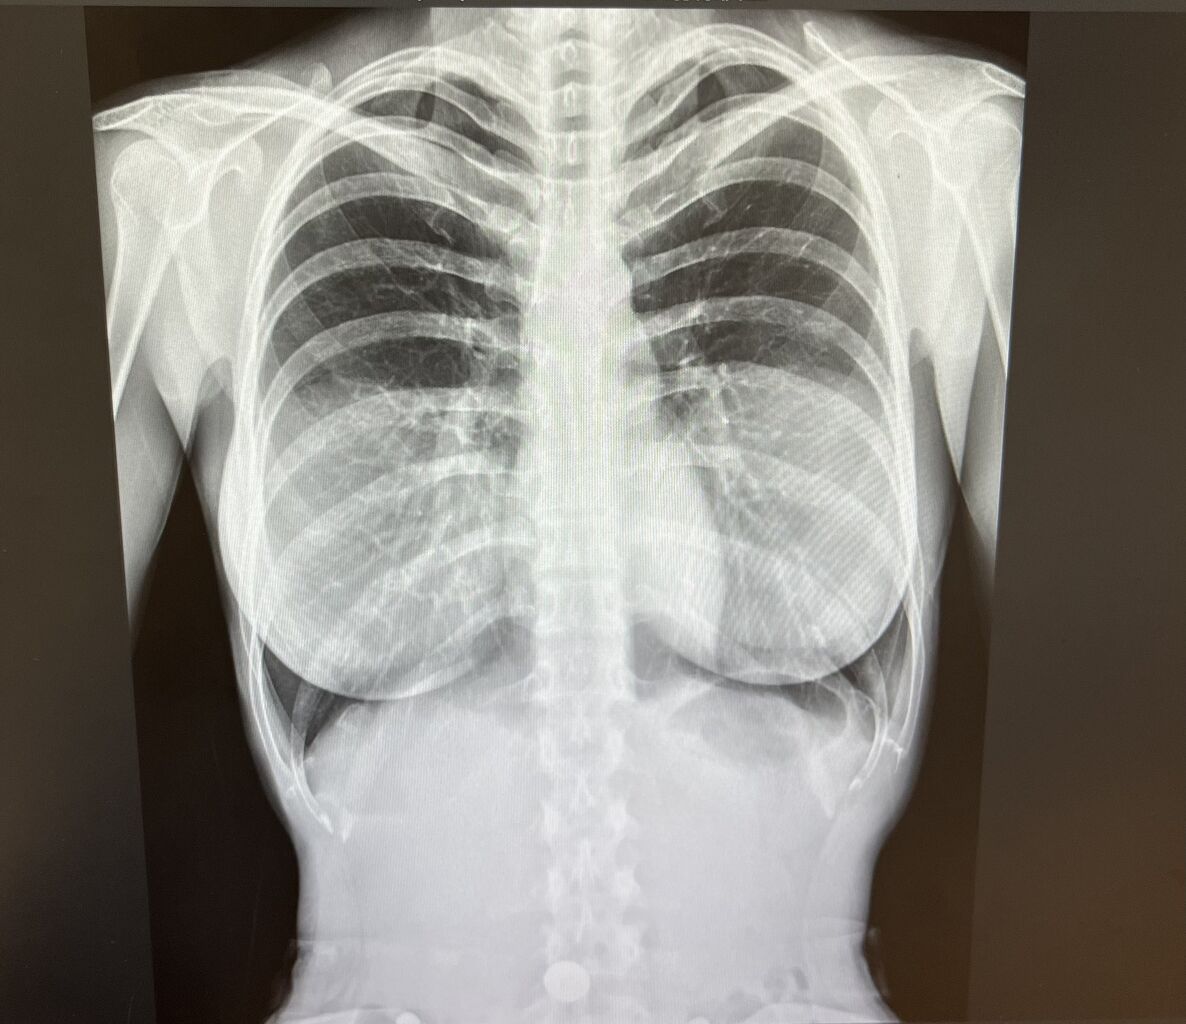

シリコンバッグ映ってて草

入れ乳だとこのように映るらしい